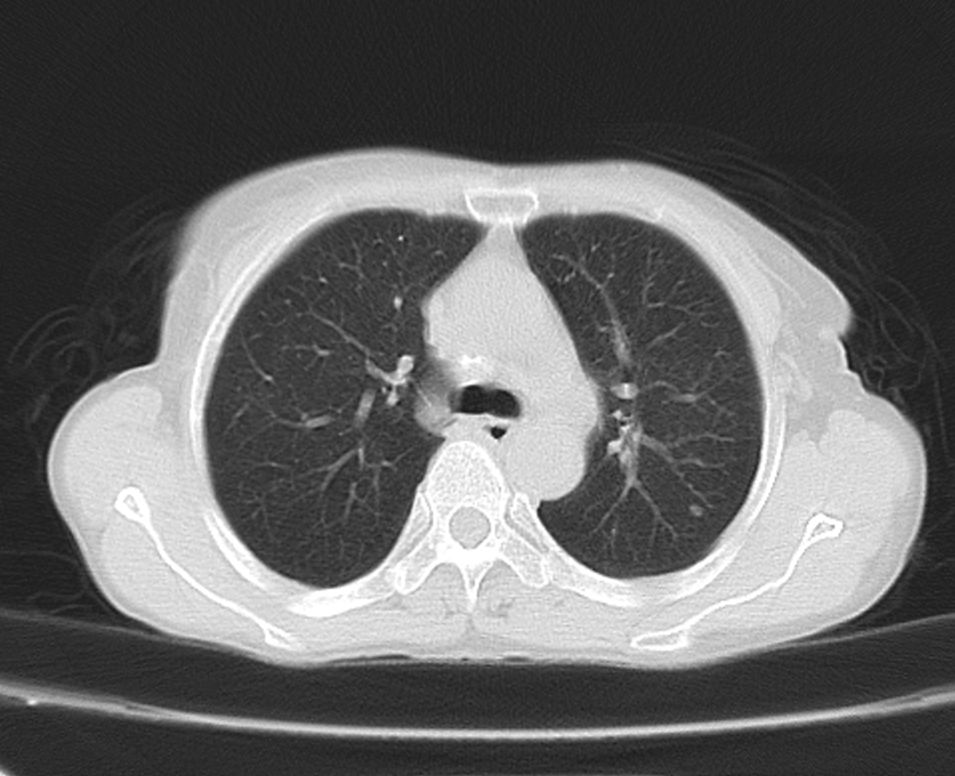

标题: CT21609:右乳包块1年,请各位讨论分析一下,乳腺CA, [打印本页]

标题: CT21609:右乳包块1年,请各位讨论分析一下,乳腺CA,

考虑---右乳癌并胸壁、肋骨、双肺转移。

考虑乳腺癌侵犯肋骨、胸壁及两肺转移可能性大。

右乳癌并胸壁、肋骨、双肺转移。

考虑右侧乳腺癌侵犯肋骨、胸壁及两肺转移。

考虑右侧乳腺癌侵犯肋骨、胸壁及两肺转移可能。

考虑右侧乳癌并胸壁、肋骨及双肺多发性转移。